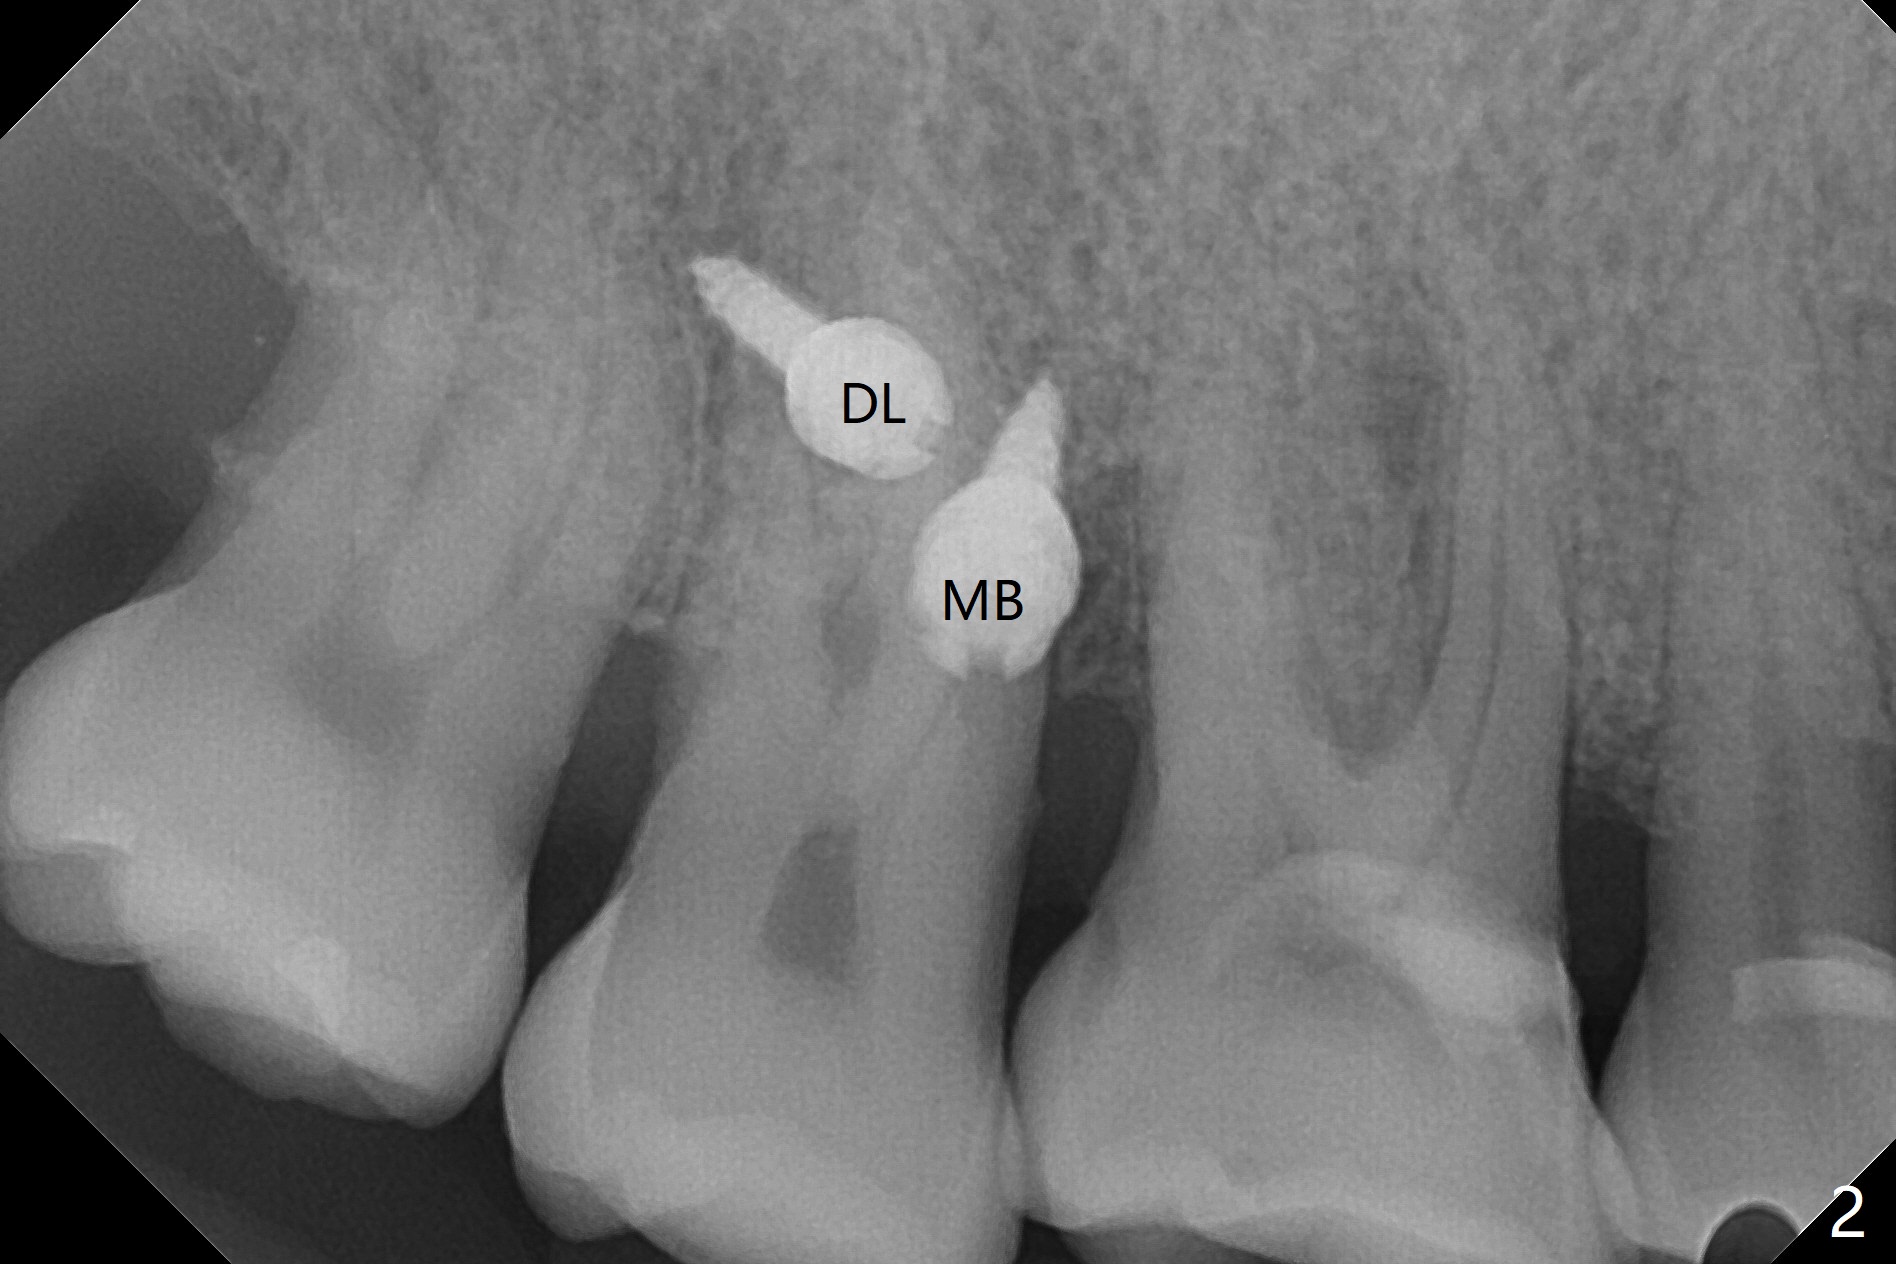

When 6 and 8 mm Tomas pins are initially placed mesiobuccal (MB) and distolingual (DL) to the supraerupted tooth #2, PA is taken (Fig.1), which shows that the DL one seems too distal. The mini implant is removed and placed more mesial (Fig.2, 7 (^: original entry)). When the patient experiences a little pain as the DL implant is being placed deeper with minimal local anesthetic, CT is taken. In fact the latter is between the apices of the teeth #1 and 2 (Fig.3 (L: lingual view of 3D image)). The implant is later placed deeper with minor angular change as well as more anesthetic. There is an advantage to place the miniimplants apically; there is more space. But the MB implant is a little bit mesial (Fig.4). After withdrawal, the trajectory of the implant is changed somewhat as indicated by a red arrow in Fig.5). Note the apical placement of the minimplants (close to mucogingival junction, Fig.6,7).